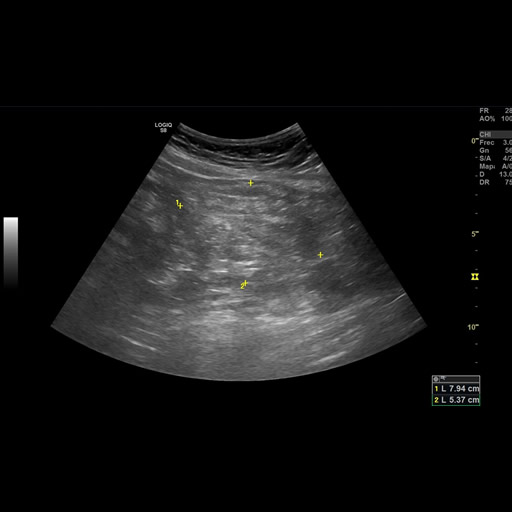

Paciente sexo masculino de 79 años, con antecedentes de HTA y diverticulosis , ingresa por presentar cuadro de lipotimia. Al ingreso refiere epigastralgia moderada y sudoración fría.